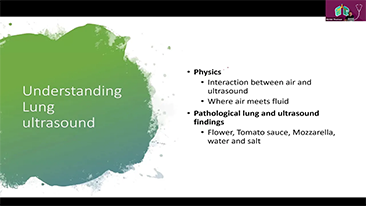

Aparaty ultrasonograficzne z serii Resona, dzi?ki szerokiej gamie za pomoc? wszechstronnych sond do r√≥?nych zastosowaŇĄ i wydajnych narz?dzi do zastosowaŇĄ klinicznych, pomagaj? U?ytkownikom stawia? dok?adniejsz? i efektywniejsz? diagnoz? oraz ocenia? wyniki.

Produkty do obrazowania ogólnego